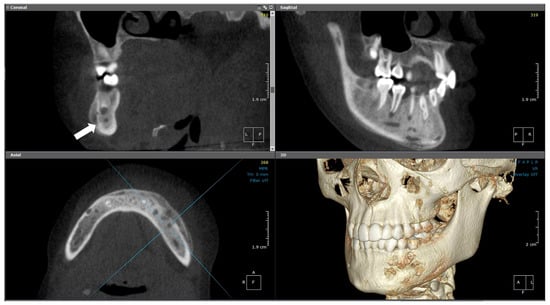

2.4.2. Radiographic Examination

| 4 | 12 | Left mandible (#37–#43, crossing midline) | Irregular mixed sclerotic/lytic lesion, periosteal reaction, buccolingual expansion | Viable bone with no bacterial colonies | Empirical antibiotics, paracetamol, NSAIDs | CNO confirmed based on recurrence, imaging, and histology | NSAIDs only; no additional therapy needed | Gradual clinical improvement; no recurrence noted |